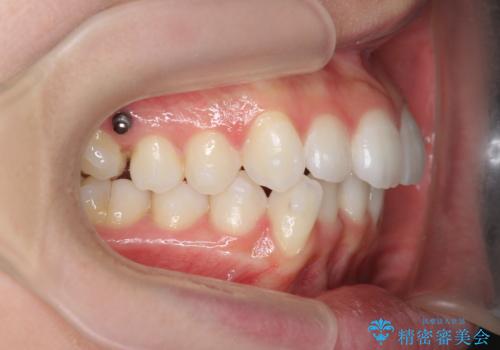

- 前歯が出っ歯のように見えることの改善を求めて来院されました。

当初、セラミックによる治療をご希望されていましたが、相談の結果矯正治療を選択されることとなりました。

通常口元の突出感の改善を行うには小臼歯の4本抜歯が検討されますが、歯のガタ付きが下顎前歯に限定していることから

下顎前歯を1本だけ抜去を行い、上顎の歯は可及的にマイクロインプラントを用いた後方移動を行い口元の印象の改善を計画することとなりました。

マイクロインプラントを用いてしっかりと後方移動を行ったことで前歯の角度は改善され、口元もすっきりと仕上げることができました。